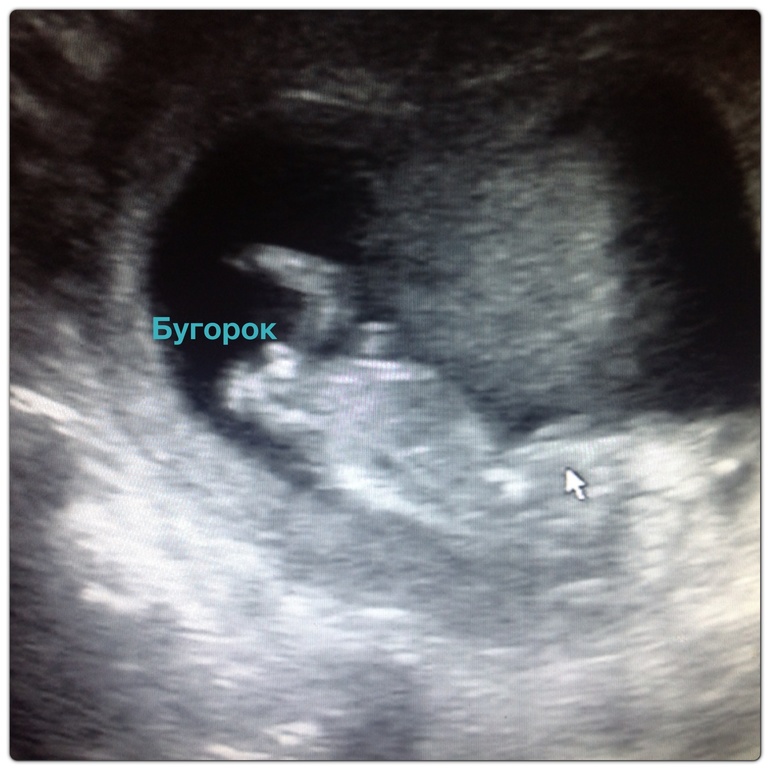

Вот смотрите мои девченк. Все узи сделан на 12-13 неделях. По вашей фотке похоже на мальчика.Это 2 доча смотрите, где стрелка

Ну блин в 22 недели конечно уже писюнчик и яички. А это узи с 12 недель и у деток еще у всех есть эти бугорки, надо определять углу наклона. У девочек вдоль позвоночника, у мальчиков угол больше 30 градусов.